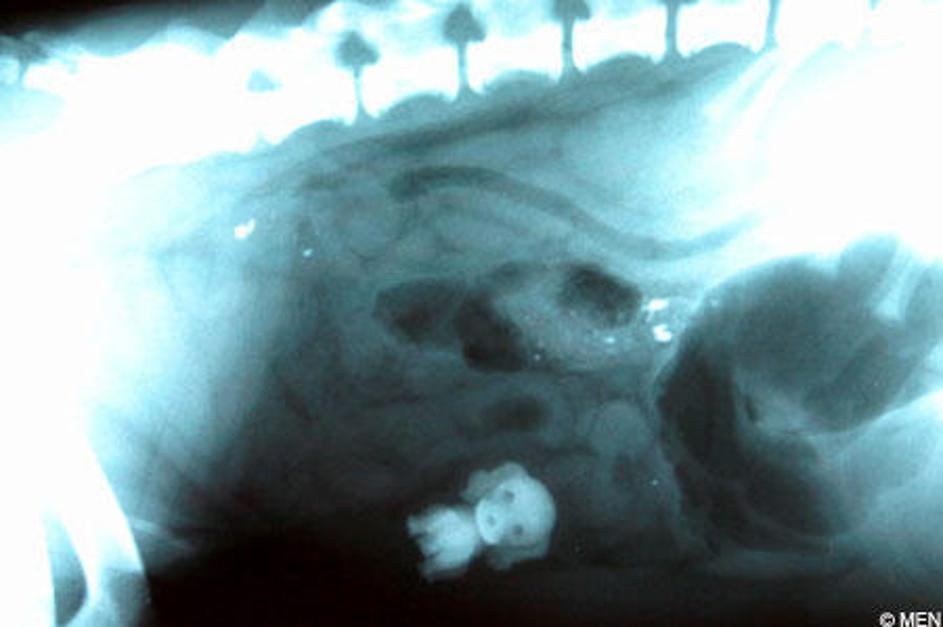

Nenavadni rentgentski posnetki

Rentgenski žarki so prvi omogočili pogled v ljudi, ne da bi jih bilo treba razre